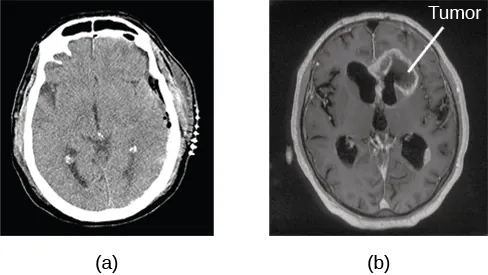

Tomografia komputerowa (TK) (ang. computerized tomography (CT)) to obraz utworzony z wielu zdjęć rentgenowskich danej części ciała (w tym mózgu) (Ilustracja 3.26). Promienie X, przechodząc przez tkanki o różnej gęstości, są tłumione w różnym stopniu, dzięki czemu komputer może stworzyć całkowity obraz badanego obszaru. TK często jest wykorzystywana do stwierdzenia, czy w mózgu badanej osoby rozwija się guz albo czy dochodzi do znaczącego zaniku tkanki mózgowej.

Ilustracja 3.26 Obraz TK może ujawnić guzy mózgu. (a) Obraz po lewej ukazuje zdrowy mózg, podczas gdy (b) ten po prawej – mózg z guzem w lewym płacie czołowym. (Źródło: ilustracja (a): modyfikacja pracy „Aceofhearts1968”/Wikimedia Commons; ilustracja (b): modyfikacja pracy Rolanda Schmitta i in.).